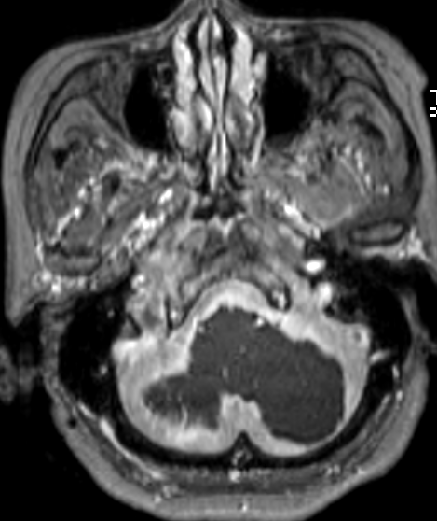

2013-5-16 MRI